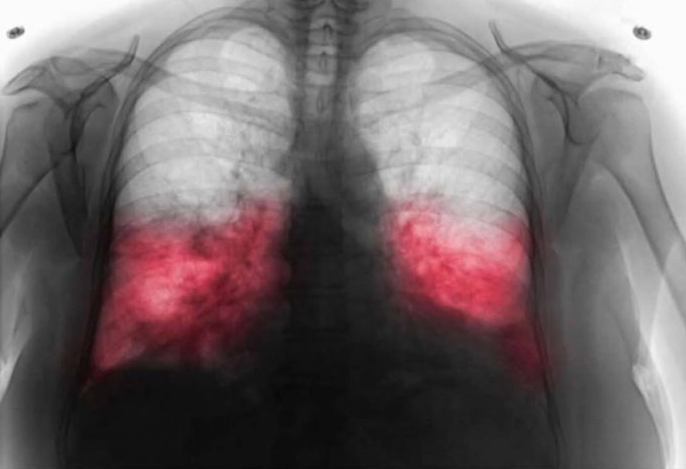

Kada postoji sumnja na hodajuću upalu pluća, ljekar će najprije razgovarati s pacijentom o simptomima i pažljivo poslušati pluća. U mnogim slučajevima potrebne su dodatne analize kako bi se potvrdila dijagnoza.

- To može uključivati laboratorijske nalaze, briseve respiratornih puteva ili rendgenski snimak pluća. Tačna dijagnoza je veoma važna, jer uzročnik ove bolesti često ne reaguje na uobičajene antibiotike koji se koriste kod drugih infekcija.